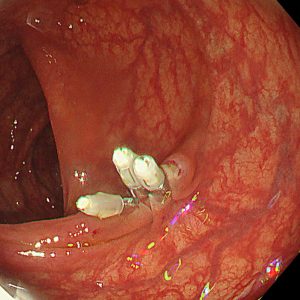

便潜血陽性を認め、人生初めての大腸カメラ検査目的で来院された方です。横行結腸に15mm大の細長いⅠp病変を認めました。拡大NBI観察では一部JNET2A、内視鏡的一括切除を行いました。回収した病変の病理結果は治癒切除でした。上記病変を含めて合計4病変、大腸内視鏡的治療をすることができました。

70歳代 男性 便潜血陽性 #.横行結腸腺腫 15mmⅠp #.多発性大腸腺腫

左:遠景NBI観察、 中:クリッピング術後、 右:病変回収時